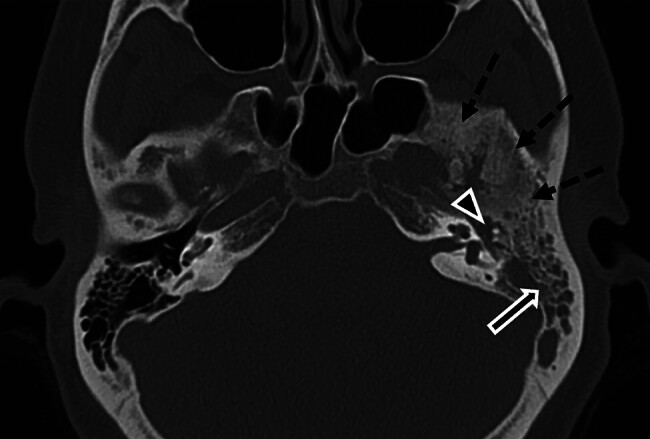

Temporal bone en plaque meningiomas can present management challenges, particularly when accompanied by severe pain. We report the case of a 42-year-old woman who was initially diagnosed with chronic otitis media but was later found to have a painful left temporal bone en plaque meningioma. Despite conservative therapy, her pain progressed, prompting the decision to undergo surgical resection, which resulted in considerable pain relief. This report illustrates the influence of pain on surgical decision-making for temporal bone en plaque meningiomas and reviews the literature on their variable presentations and management strategies.